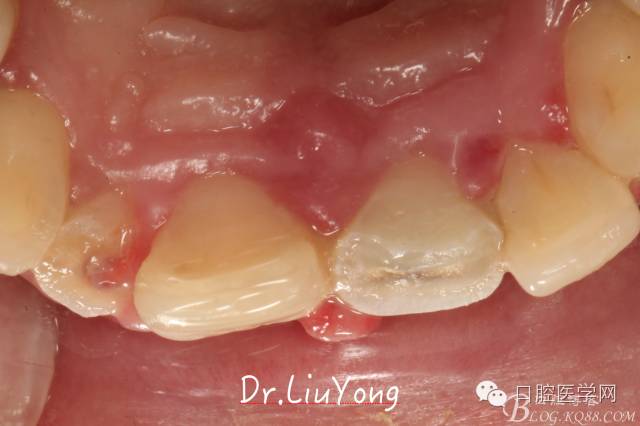

骨塊固定兩周后復(fù)查,如上圖:

在松動牙固定的同時,嘗試保留B1唇側(cè)折裂牙槽骨塊,拆除縫線后,局部沖洗,牙周塞治劑覆蓋并固定游離骨塊。囑患者加強口腔衛(wèi)生,氯己定漱口液含漱,兩周后復(fù)查。兩周后拆除塞治劑,骨塊仍為游離活動狀態(tài),去除游離骨塊,局部沖洗上藥。